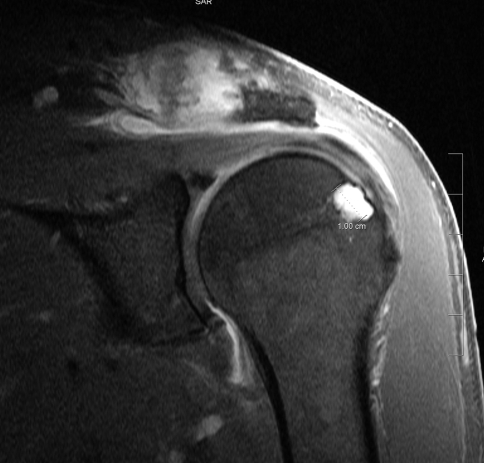

Schmid et al. reported that the MR imaging appearance of three ankle joints with primary hemochromatosis, containing extensive subchondral cyst formation, subchondral sclerosis, and joint space narrowing [3, 6]. In our case MRI of shoulder shows a 1 cm erosion of humeral head (Fig. 2).

Fig. 2.

Hemochromatosis of the shoulder. Coronal T1 fat-saturation post-contrast image (580/13) of the left shoulder shows a 1-cm erosion of the humeral head with contrast enhancement. Erosion and synovial enhancement are at the AC joint. There is enhancement of the subacromion subdeltoid bursa due to bursitis